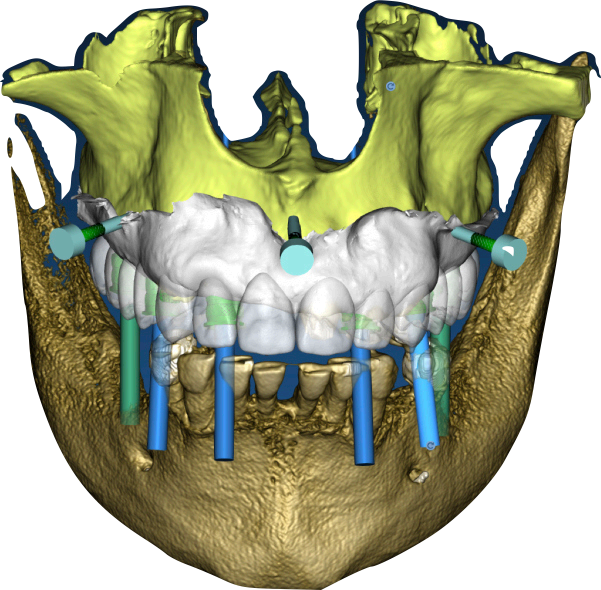

Initial diagnostic workup included a comprehensive radiographic evaluation using cone-beam computed tomography (CBCT) to assess bone volume and quality at the proposed implant sites: 16 (upper right frst molar), 14 (upper right frst premolar), 12 (upper right lateral incisor), 22 (upper left lateral incisor), 24 (upper left frst premolar), and 26 (upper left frst molar). The CBCT confrmed suffcient bone height and width to support six implants without the need for extensive grafting, though minor bone leveling was anticipated. Digital impressions were acquired using the Shining3D Elite intraoral scanner, capturing detailed surface anatomy of the maxilla and remaining teeth. A 3D facial scan was also performed to integrate smile design principles, ensuring the prosthetic outcome aligned with the patient’s facial aesthetics (Fig. 1.3). A digital wax-up was created in Exocad, simulating the fnal prosthesis with attention to tooth proportions, midline alignment, and lip support. After patient approval, this wax-up served as the foundation for implant planning (Fig. 1.4, 1.5).

The treatment objective was a maxillary full-arch FP1 restoration, characterized by a fxed prosthesis that replaces only the dental crowns, preserving a natural gingival appearance without artifcial gingiva. Six implants were strategically planned at positions 16, 14, 12, 22, 24, and 26 to distribute occlusal forces evenly and support a zirconia prosthesis with a metallic iBar framework. The implant positions were determined prosthetically, guided by the digital wax-up to ensure that the fnal restoration would align with the patient’s aesthetic and functional goals.

A stackable surgical guide was designed to streamline the surgical phase and facilitate immediate provisionalization. This guide consisted of multiple components, including a fxation bar that served as the central fduciary element, osteotomy guides for precise drilling, and a framework for aligning the provisional prosthesis (Fig. 2.1). The guide was fabricated using a 3D printer with biocompatible resin on the day of surgery, ensuring a tailored ft based on the latest digital data. The provisional prosthesis was pre-designed with a scalloped emergence profle to shape the soft tissues during healing, promoting a festooned gingival contour that would enhance the fnal aesthetic result. This immediate loading approach was chosen to provide the patient with a functional and aesthetic solution on the day of surgery while establishing a foundation for long-term tissue adaptation.

Group 2: Surgical Procedure Fig. 2.1: 3D model of the stackable surgical guide with fxation bar. Fig. 2.2: Occlusal view of the osteotomy guide in use during surgery. Fig. 2.3: Frontal intraoral view post-implant placement with MUAs attached. Fig. 2.4: Occlusal view of coded scan body captured by Shining3D Elite photogrammetry.

The surgical procedure was performed under local anesthesia in a single session. The residual roots at 13 and 21, along with the fractured teeth at 22 and 13, were extracted with minimal trauma to preserve the surrounding bone and soft tissue. The stackable guide was secured intraorally using the fxation bar anchored to the maxilla, providing a stable reference for implant placement (Fig. 2.2). Osteotomies were prepared at the planned sites (16, 14, 12, 22, 24, 26) using the guide’s drilling sleeves, ensuring accuracy in depth and angulation. Six implants were inserted, and multi-unit abutments (MUAs) were immediately placed to facilitate prosthetic connection (Fig. 2.3).

Following implant placement, intraoral photogrammetry was performed using the Shining3D Elite scanner. Scan markers were attached to the MUAs, and their positions were captured with high precision (Fig. 2.4, 3.4). Multiple scans were acquired, including the maxillary arch (Fig. 3.1), the fxation bar from the stackable guide (Fig. 3.2), the MUAs (Fig. 3.3), and the surrounding soft tissues (Fig. 3.5). The photogrammetry data was merged with conventional intraoral scans, using the fxation bar as a fduciary to align all datasets accurately (Fig. 3.7). A heat map generated in the software confrmed the precision of this alignment, with minimal discrepancies across the arch (Fig. 3.7). The scan markers were then converted to implant-specifc analogs compatible with the chosen implant system (Fig. 3.6).